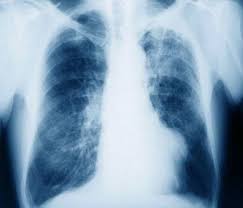

Mesothelioma is a preventable but fatal form of cancer that develops in the protective membrane known as the mesothelium, a layer of tissue that covers most internal organs. Mesothelioma is the result of asbestos exposure, and the individual types of mesothelioma are named for specific mesothelium in which the cancer exists.

- Pleural mesothelioma: Develops in the pleura, the mesothelium surrounding the lungs; the most common type of mesothelioma